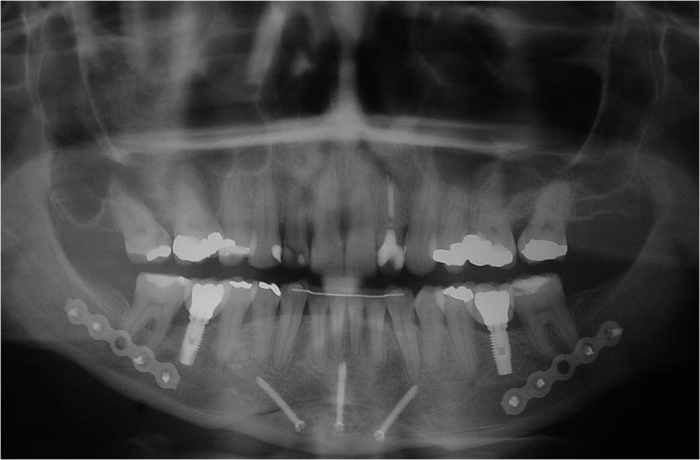

Raio x inicial